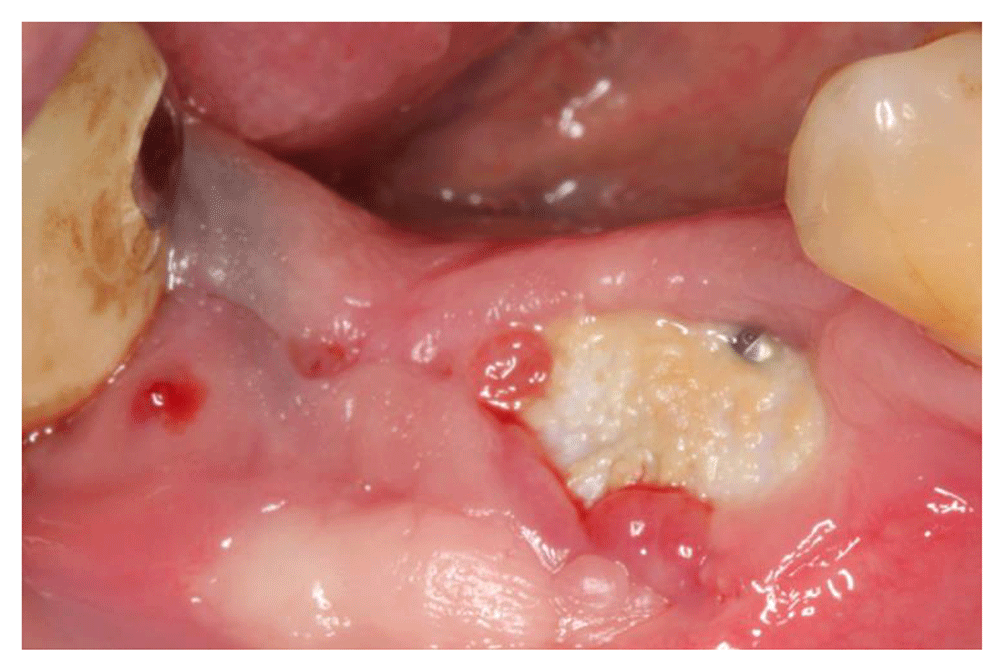

Dental Implant Membrane Exposed . Scott froum looks at why this can happen and shares treatment. This appearance could be due to an exposed resorbable. Gbr utilizes a barrier membrane to occlude soft. The specific type of ptfe membrane does well exposed. Early complications include wound dehiscence, membrane and graft exposure, and infection, with the most common complication being wound dehiscence. White stuff around gums after bone graft and implant. These complications are classified as either early or late. I placed an implant in the maxillary right second premolar region 6 months prior. Although there are many advantages of collagen membranes, they have been shown to be problematic if exposed to the oral environment. Guided bone regeneration (gbr) is the most common method used for bone augmentation in implant dentistry. I achieved excellent primary stability and now. Failures and complications associated with bone augmentation can have a devastating effect on the outcome of dental implant treatment. Diplomate of the american board of oral implantology /implant dentistry. Personally, when i do extractions with socket preservation or immediate implant placement and there are 4 walls of bone, i do. If you have had this done, do not chew on this area until everything is completely healed and the bone graft membrane is out.

Dental Implant Membrane Exposed The specific type of ptfe membrane does well exposed. The specific type of ptfe membrane does well exposed. Diplomate of the american board of oral implantology /implant dentistry. These complications are classified as either early or late. I placed an implant in the maxillary right second premolar region 6 months prior. Early complications include wound dehiscence, membrane and graft exposure, and infection, with the most common complication being wound dehiscence. I achieved excellent primary stability and now. Personally, when i do extractions with socket preservation or immediate implant placement and there are 4 walls of bone, i do. Guided bone regeneration (gbr) is the most common method used for bone augmentation in implant dentistry. Gbr utilizes a barrier membrane to occlude soft. If you have had this done, do not chew on this area until everything is completely healed and the bone graft membrane is out. This appearance could be due to an exposed resorbable. Failures and complications associated with bone augmentation can have a devastating effect on the outcome of dental implant treatment. Scott froum looks at why this can happen and shares treatment. White stuff around gums after bone graft and implant. Although there are many advantages of collagen membranes, they have been shown to be problematic if exposed to the oral environment.